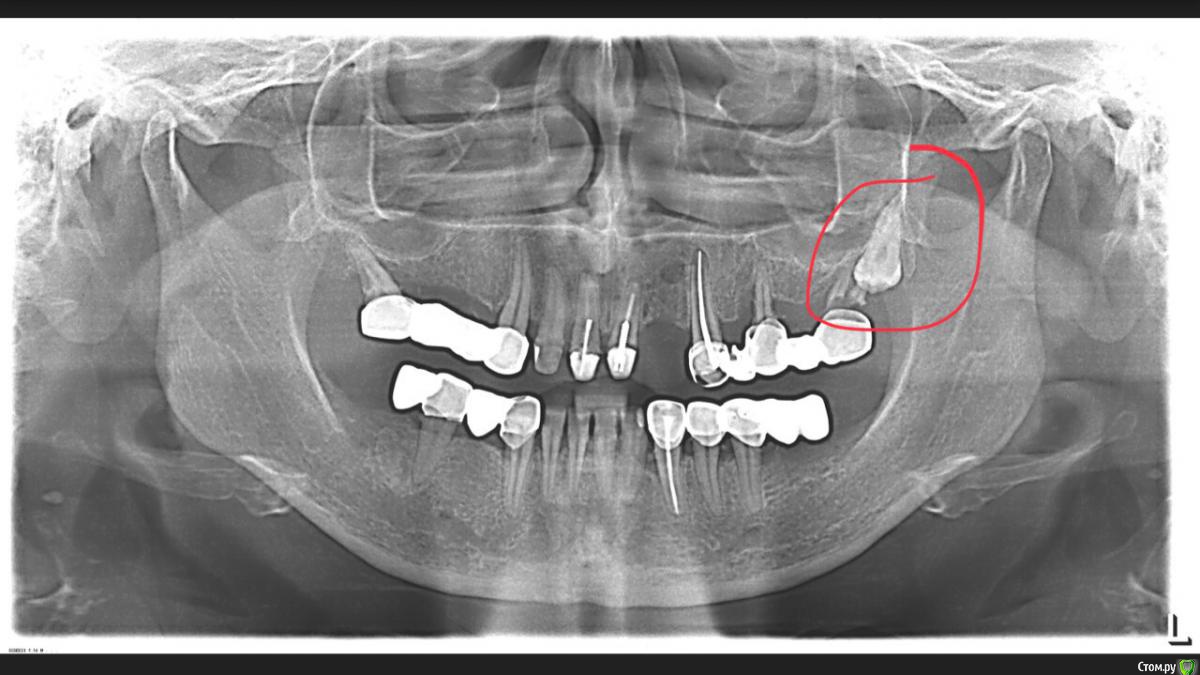

dr.Dre Опубликовано 12 февраля, 2018 Поделиться Опубликовано 12 февраля, 2018 Добрый вечер , коллеги что можете сказать , стоит ли его вырывать не тревожит, планируется имплантация. Ссылка на комментарий

kramer Опубликовано 13 февраля, 2018 Поделиться Опубликовано 13 февраля, 2018 Достаёте корни 27, дальше 28 как на ладони 1 Ссылка на комментарий

Борис80 Опубликовано 13 февраля, 2018 Поделиться Опубликовано 13 февраля, 2018 27 на удаление? 28 следом выйдет без проблем Ссылка на комментарий